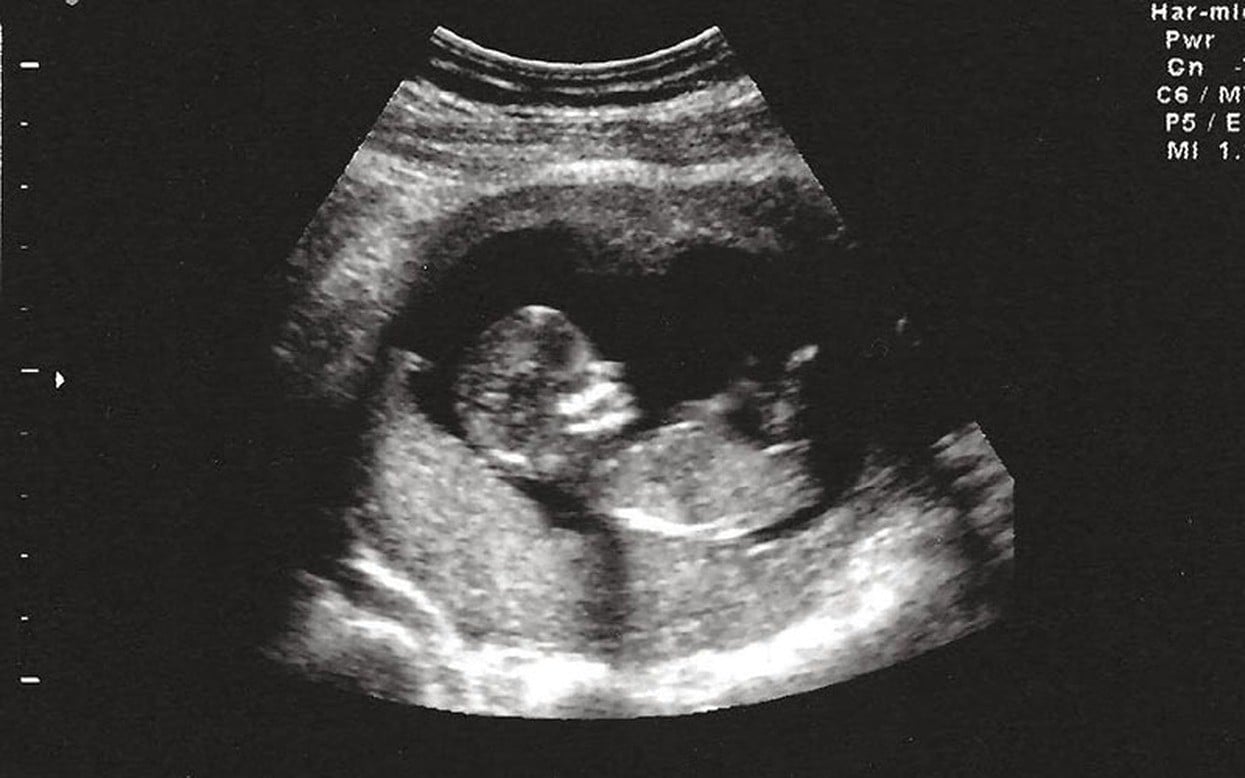

Đến lần mang thai thứ 5, em làm xét nghiệm NIPT, kết quả bình thường, em thở phào nhẹ nhõm. Em tin, có lẽ ông trời đã thương. Nhưng đến tuần thứ 20, bác sĩ nói chân tay con bị khèo… rồi mọi hy vọng lại sụp đổ thêm lần nữa.

"Lúc cầm tờ kết quả xét nghiệm chẩn đoán, em chỉ biết khóc. Không còn nước mắt nào đủ để rơi nữa." Lần này, em làm NIPT kèm xét nghiệm sàng lọc gen, em mới biết cả hai vợ chồng đều mang cùng một gen bệnh lặn – và có 25% khả năng con sinh ra bị bệnh di truyền. Bác sĩ bảo, đó chính là nguyên nhân khiến con không thể ở lại.

Bao gồm: Double test, Triple test, NIPT, siêu âm hình thái, v.v.

Nếu có nghi ngờ bất thường, bác sĩ sẽ chỉ định thêm xét nghiệm di truyền chuyên sâu hoặc xét nghiệm gen của bố mẹ.